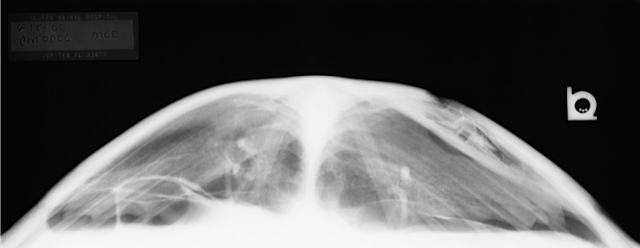

- Loss of intestinal motility is termed ileus. This decrease in peristalsis may be due to intestinal atony related to infection or dehydration, loss of neurologic function and subsequent paralysis, or bowel obstruction. Note gas dilated loops of intestine compressing the dorsal lung fields in this AP view.

- Aspiration pneumonia is commonly seen as a "fog line" on the AP view with normal lung above and below. It is typically bilateral.

- Pneumonia will appear as increased soft tissue density focused along the primary bronchi. It may affect both lungs but most commonly only one. *Severely debilitated or cold stunned turtles may behaviorally float due to breath holding.